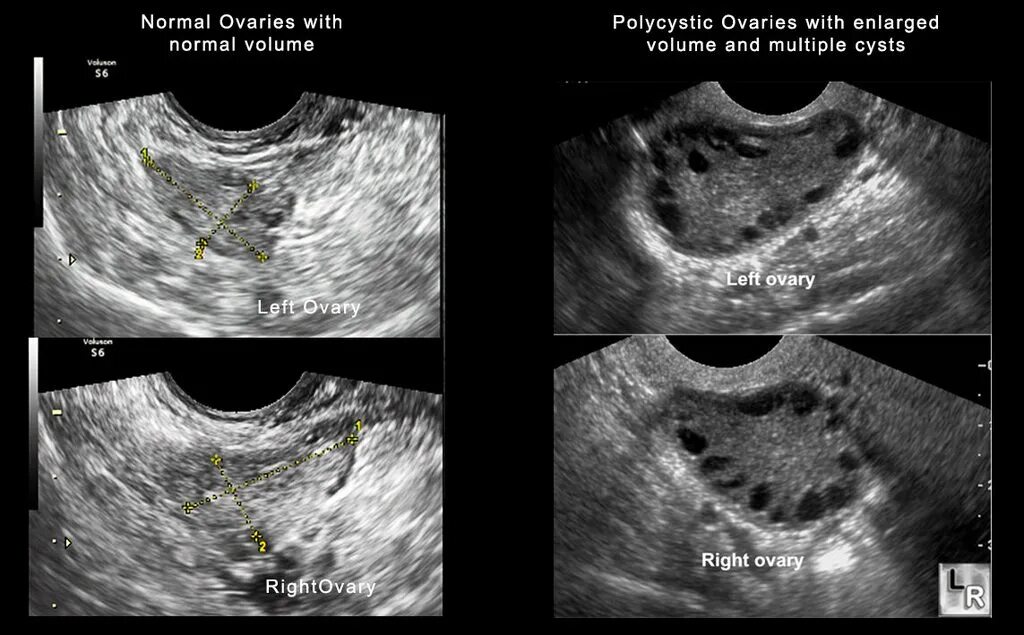

Фолликул 26 мм